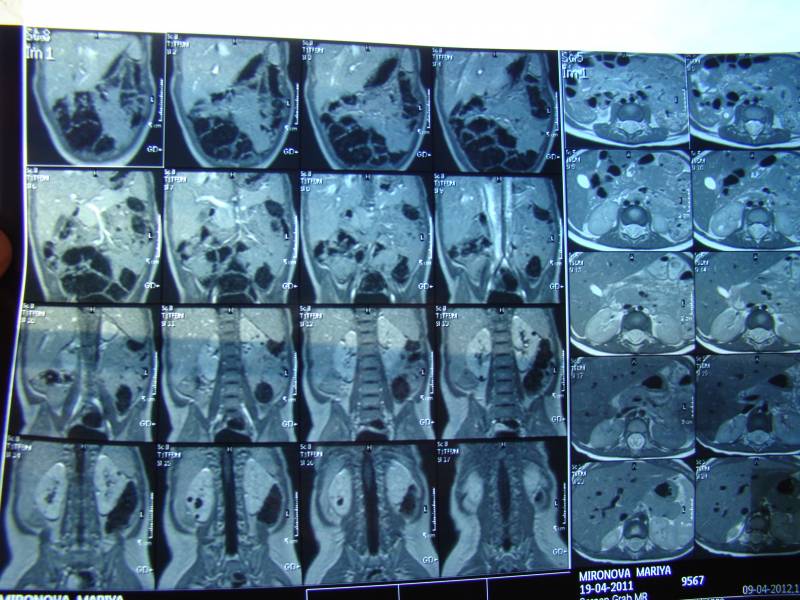

снимки